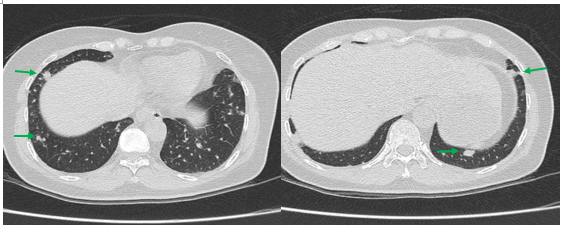

- Chụp cắt lớp vi tính lồng ngực: Nhu mô thùy trên phổi (Phải) có nốt tổn thương kích thước 13x14mm,bờ không đều, ngấm thuốc, sau tiêm. Rải rác nốt đặc 2 bên thùy phổi kích thước 3-10mm. Trung thất các nhóm 1R; 2R; 4R; 5; 8; 10RL có vài hạch lớn nhất kích thước 26x15mm; bờ không đều; ngấm thuốc không đồng nhất sau tiêm. Thượng đòn 2 bên có vài hạch tính chất tương tự; hạch bên phải kích thước 11x14mm

Hình 1.

Hình ảnh cắt lớp vi tính ngực có tiêm: thùy trên phổi (P) có nốt tổn thương kích thước 13x14mm, bờ không đều, ngấm thuốc, sau tiêm. Nghi ngờ tổn thương nguyên phát (mũi tên đỏ)

Hình 2: Hình ảnh cắt lớp vi tính ngực có tiêm: Rải rác nốt đặc 2 bên thùy phổi kích thước 3-10mm (các mũi tên màu xanh lá)

- Cắt lớp vi tính lồng ngực: đám xẹp đông đặc đỉnh phổi phải kích thước 11mm; nhu mô phổi rải rác nốt đặc 5-10mm. Trung thất cân đối có vài hạch 10mm

Hình 6: Hình ảnh cắt lớp vi tính ngực có tiêm: đám xẹp đông đặc đỉnh phổi phải kích thước 11mm (mũi tên xanh nước biển)

Hình 7: Hình ảnh cắt lớp vi tính ngực có tiêm: Trung thất cân đối có vài hạch 10mm (mũi tên vàng). Hạch trung thất giảm kích thước rất nhiều chỉ sau 03 chu kỳ.

- Cắt lớp vi tính lồng ngực: Đám xẹp vùng đỉnh phổi phải, nốt đặc nhỏ kích thước 2-3mm. Không thấy hạch to hay khối trong trung thất

Hình 10: Hình ảnh cắt lớp vi tính ngực có tiêm: Đám xẹp vùng đỉnh phổi phải, nốt đặc nhỏ kích thước 2-3mm

Hình 11: Hình ảnh cắt lớp vi tính ngực có tiêm: Không thấy hạch to hay khối trong trung thất